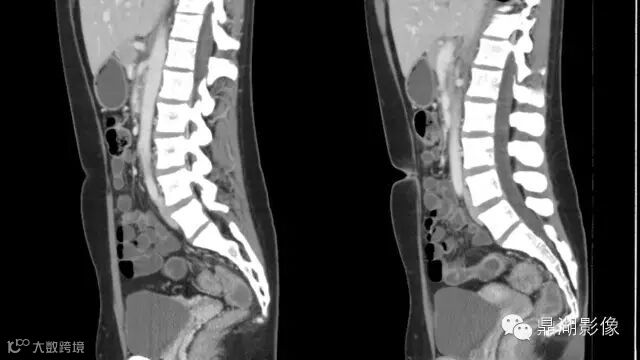

what's the meaning of fat halo sign?

粘膜下水肿或脂肪沉积,可致肠壁内呈低密度层(halo征),其最初用来描述溃疡性结肠炎,是良性肠道病变的结果,无特异性,也可存在于放射性肠炎,移植-受体疾病和慢性缺血性肠炎以及单性的肥胖症患者。

Fat halo aslo can be seen in normal terminal ileum.

It is the comb sign the most specific sign for crohn's disease.